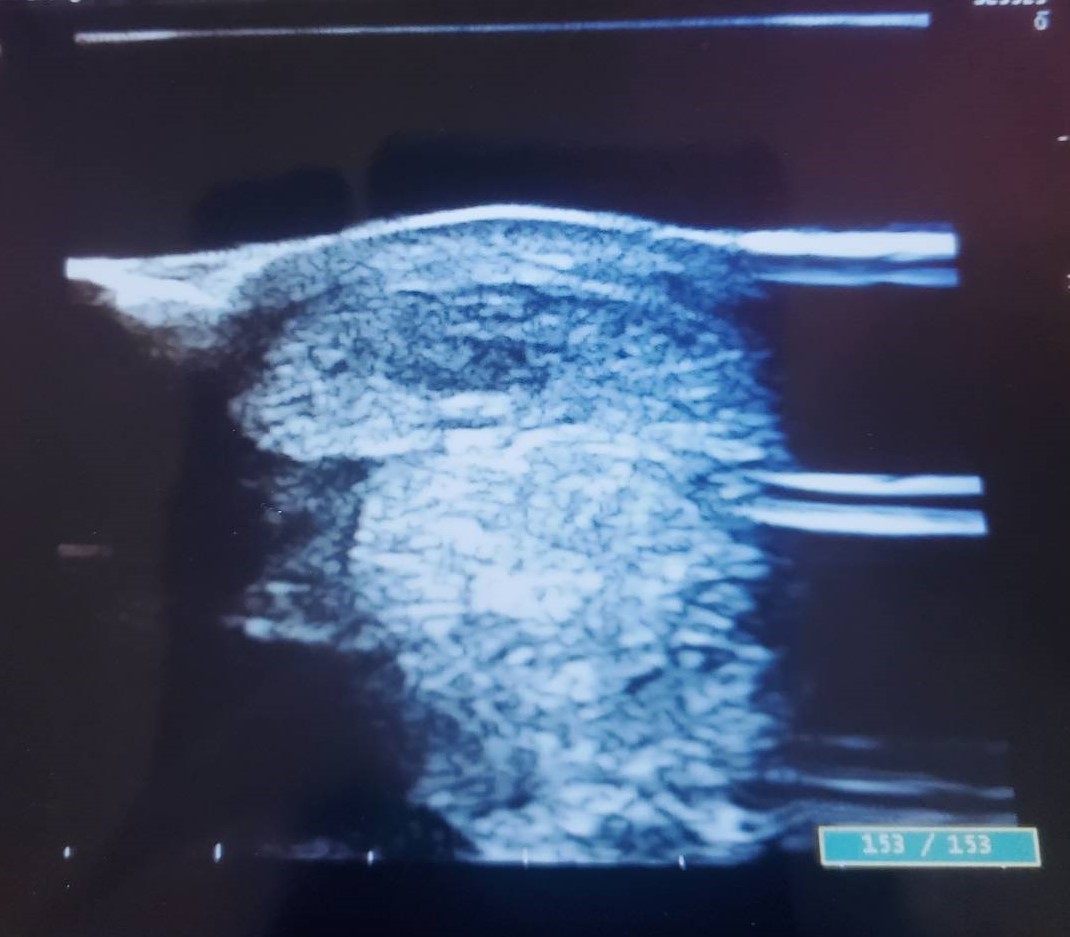

長距離のレースが合う馬でスタミナは豊富。他場へ移籍で降級しますし、脚元さえしっかり固まればまだまだ活躍できる馬です。前走後、左前脚が少し腫れた為、エコー検査をしたところ、12%という診断結果を踏まえて、オークション出品という決断をしました。添付の画像をご確認ください。

前走後に左前脚が少し腫れたので、念の為エコー検査をしたところ、12%という診断を受け、オークション出品に至りました。現在、熱感が少しありますが、痛みや歩様には出ていません。水冷にて対処しています。能力が非常に高い馬で、長距離の重賞戦線で良いところがあると思っていた馬。脚元が治れば間違いなく活躍できる馬でしたので、正直なところ、後ろ髪を引かれる思いです。(盛岡競馬・飯田弘道調教師)

※2020年5月26日(前走)に左前脚に屈腱炎(損傷率12%)を発症しています。